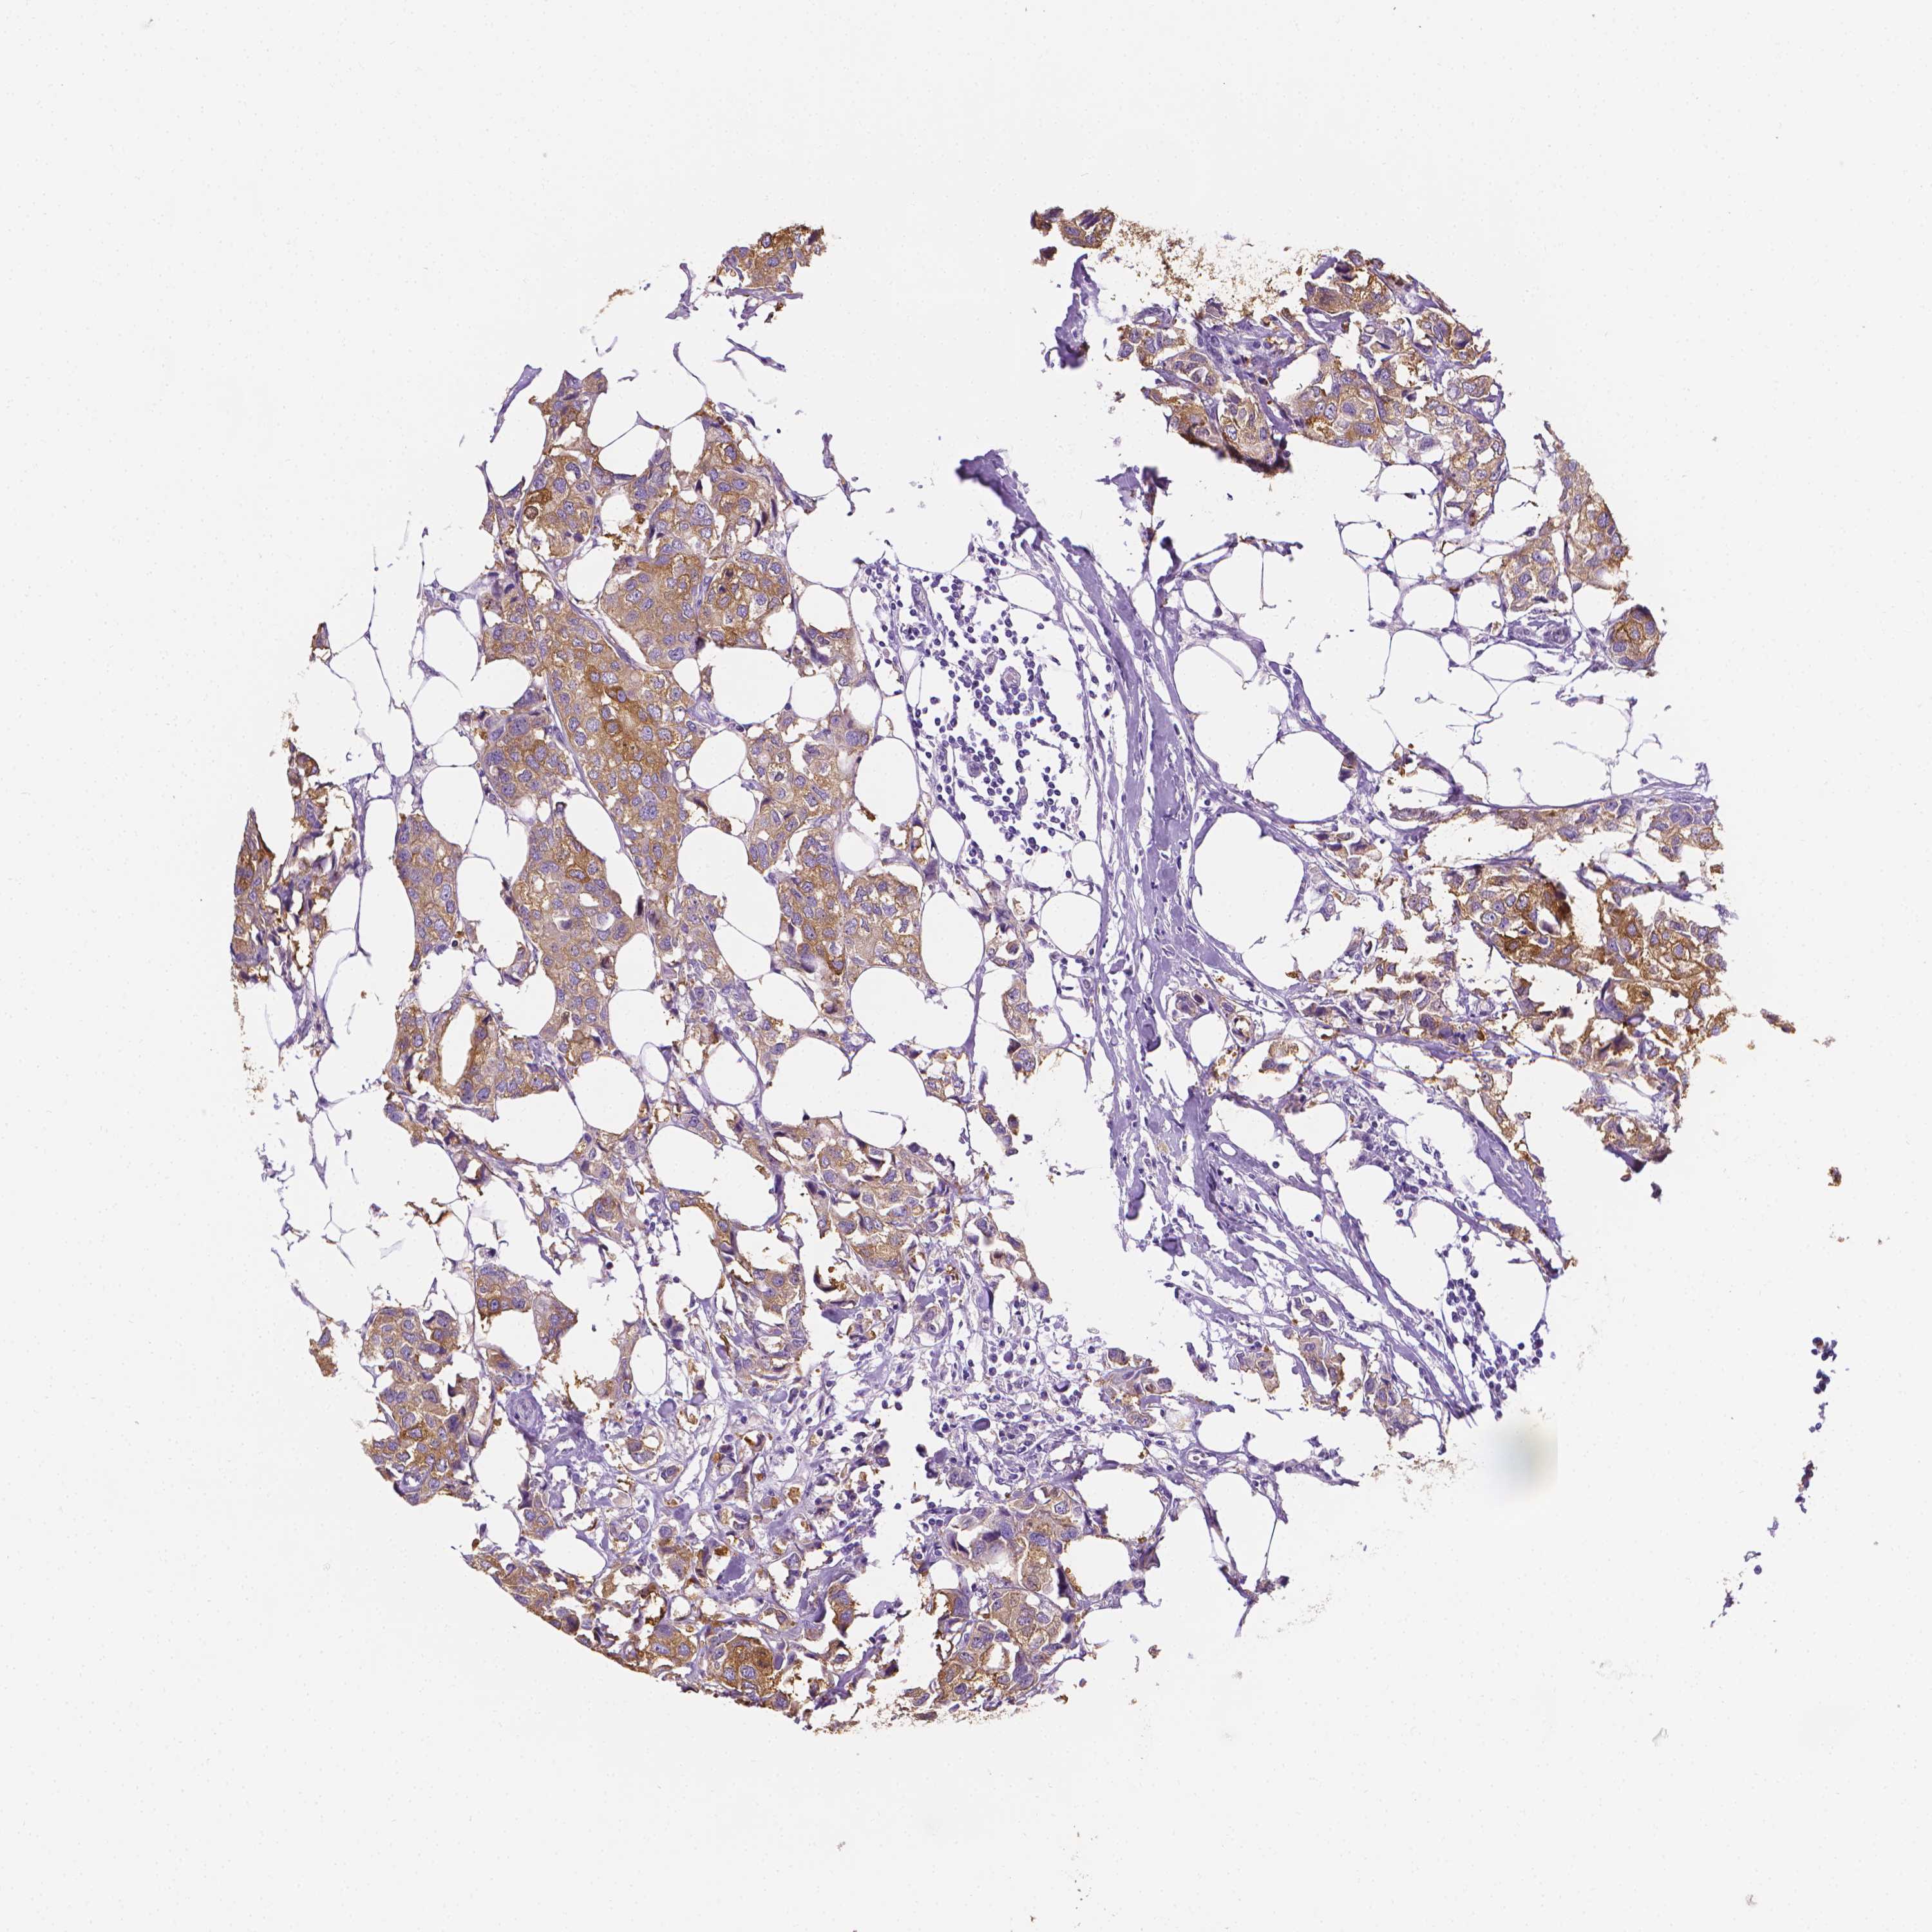

CANCER BREAST CANCER Show tissue menu

BRCA TCGA BRCA VALIDATION PROTEIN EXPRESSION

ANTIBODIES

AND

VALIDATION